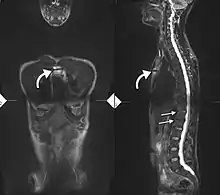

If these criteria still do not give a compelling diagnosis magnetic resonance imaging (MRI) may be useful.[22][23] MRI can show inflammation of the sacroiliac joint.

T1-weighted MRI with fat suppression after administration of gadolinium contrast showing sacroiliitis in a person with ankylosing spondylitis